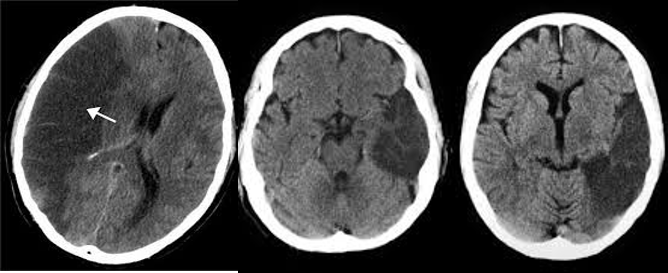

Hyperdense middle cerebral artery sign in stroke

CT head (without contrast; axial plane)

The left middle cerebral artery is hyperdense as a result of thromboembolic occlusion. Hypodensity with loss of gray-white matter differentiation in the left frontal, temporal, and parietal regions corresponds to an acute infarct in the middle cerebral artery distribution.

Dense artery sign

Dense basilar artery and middle cerebral arteries on CT

Thrombus in vessel is hyperdense relative to flowing blood